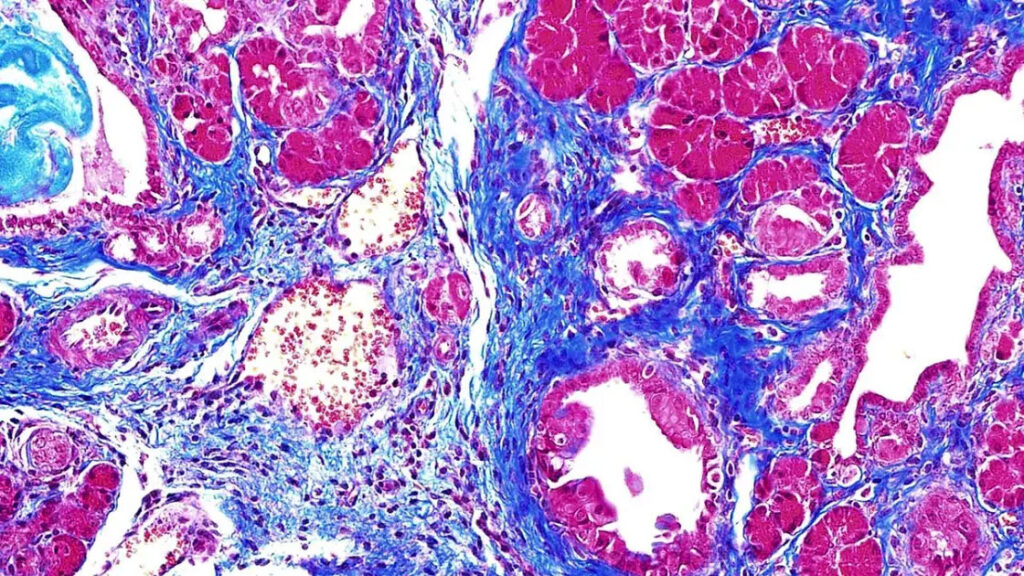

Tim mengeksplorasi peran RNA splicing, yaitu proses genetik yang terjadi sebelum produksi protein, dalam kanker pankreas. Tim menemukan protein yang disebut SRSF1, yang membantu mengatur proses RNA splicing. Mereka menemukan tingkat tinggi SRSF1 menyebabkan peradangan, juga dikenal sebagai pankreatitis.

Level SRSF1 dalam tubuh harus tetap pada tingkat tertentu dan ada sejumlah gen dan protein yang bekerja sama untuk mencapainya. Namun, karena beberapa faktor, proses ini kadang-kadang bisa menjadi tidak teratur. Hal ini sayangnya menyebabkan peradangan, yang sering mengakibatkan pembentukan tumor kanker duktus pankreas (PDAC).

Tim ilmuwan melakukan studi mereka pada model hewan. Mereka menemukan bahwa ketika SRSF1 kembali pada tingkat normal, organoid (versi kecil dari tumor) berhenti tumbuh.